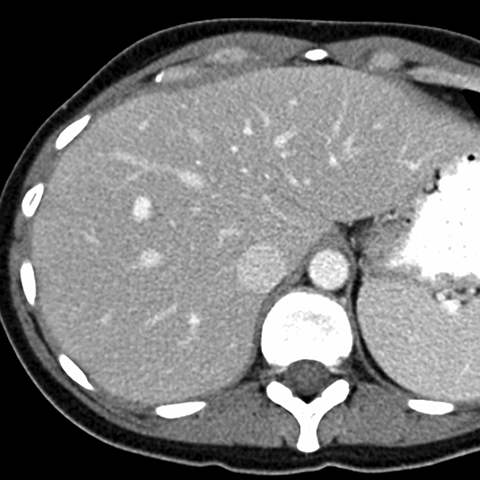

Normal Liver, CT ( axial ) [2 of 9]